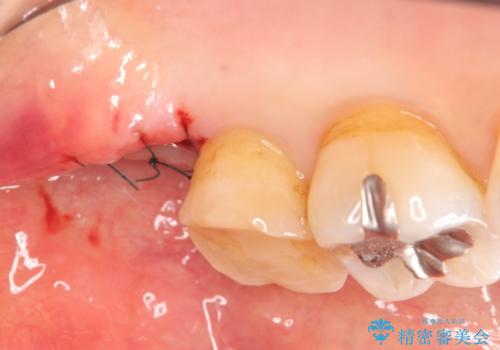

クラウンの将来的な虫歯の再発を防ぐために周囲の歯ぐきを切除することで歯の高さを出し安定した歯周環境にしたのち噛み心地の良いゴールドクラウンを製作します。

クラウンを装着した歯の虫歯の再発を防ぎ長い予後を期待するために削った箇所をしっかりとかぶせる適合の良さが必要はもちろんですが、セメントの漏洩を防ぐためにクラウンの十分な支台高径を歯周外科を行い獲得しました。